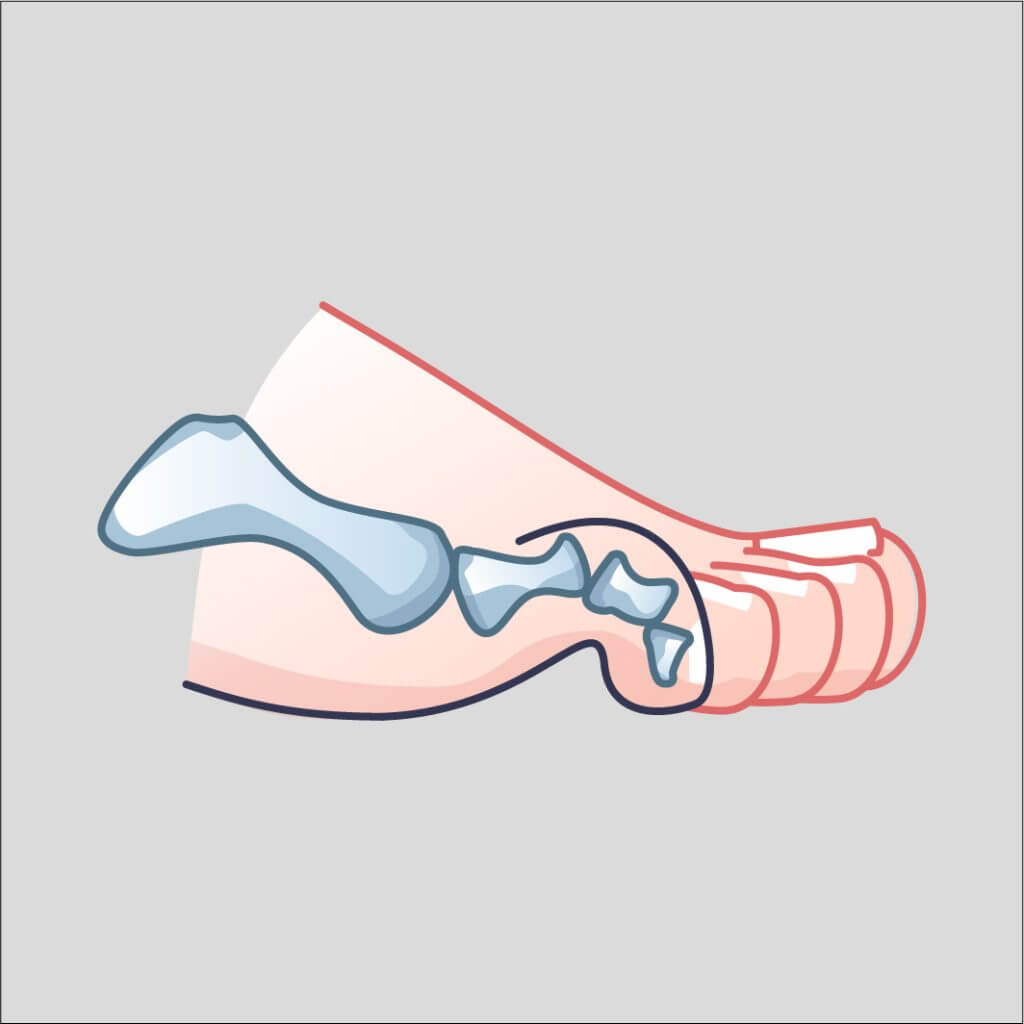

Arthritis at the 1st metatarsophalangeal joint, presenting with stiffness and pain during toe-off in gait. Managed initially with stiff-soled shoes, activity modification, orthotics; surgical options include fusion if conservative therapy fails.

Fusion of the big toe joint to reduce pain and improve function in hallux rigidus.